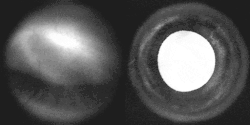

Iris, front view

Fluorescein angiograpy of the iris reveals a radial layout of blood vessels.